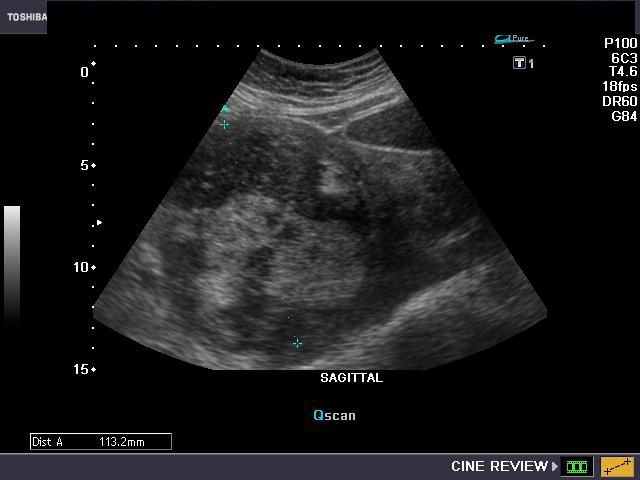

F) Degenerative changes in fibroid (degenerating fibroid)

Fibroids can undergo various degenerative changes, especially when large. This fibroid of the uterus measures 11.2 cms. and shows multiple hypoechoic and hyperechoic patchy areas

Color and Power Doppler images

here is little vascularity within the huge tumor of the upper uterus (fundus and body). Degenerative changes can take place in fibroids with areas of necrosis and hemorrhage and result in varying appearances from cystic to inhomogenous appearances. In fact, it may be difficult to differentiate a large complicated ovarian cyst from a degenerated fibroid.